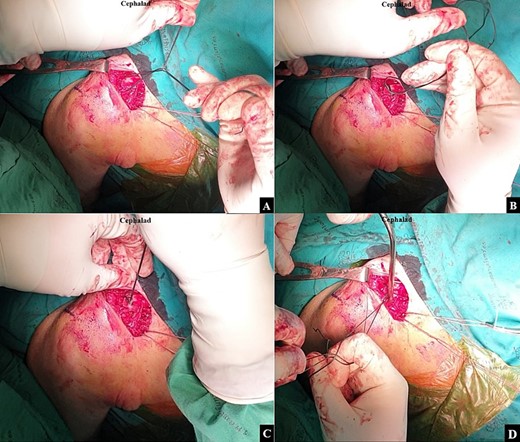

After the doubled-suture of Ethibond No.5 was passed around the coracoid base and proximal fragment of the clavicle, (A) a single square knot was thrown. (B) The two open ends of the Ethibond No.5 were passed through the loop. (C) The knot was dressed and slid down by pulling the two open ends of the Ethibond No.5. (D) A Nice knot was slowly tightened to incrementally slide the proximal fragment to the correct alignment with the distal fragment for the closed reduction.